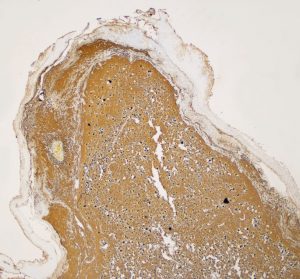

病理所見では,幼児型のpilomyxoid astrocytomaの部分が混在します。その部分が増殖と腫瘍増大に関わっています。T2強調画像で高信号でガドリニウム増強される部分です。

myxoidな部分です。右下のMIB-1染色では3%ほどの陽性率であり,数年単位では腫瘍増大があり得ることを示します。柔らかく出血性で吸引摘出できる部分の腫瘍です。IDH wild type, BRAFV600 wild type, H3K27 wild type, FGFR1 N546K mutationでした。

厚く肥厚した視神経鞘の内部の視神経組織はほとんど腫瘍に置き換わっていて,GFAPで染色され高度の石灰化を伴います。これは腫瘍というよりも瘢痕化してしまった,adult-type pilocytic astrocytomaに認められる所見です。

Rosenthal fiber, eosinophyric granular body, psammoma bodyなどが認められ,成熟しきって退行変性に移行するpilocytic astrocytomaの像です。この部分は増大しません。線維性に極めて硬い組織です。